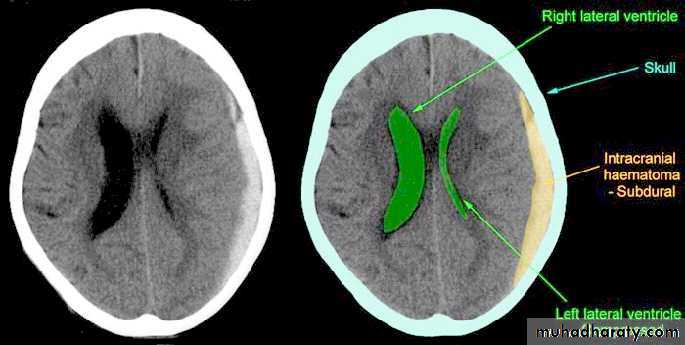

b. Subdural Haematoma

They are the most common intracranial mass lesions resulting from head trauma.They are classified depending on how long they take to present clinically following the injury into:

Acute Subdural Haematoma: less than 3 days

Subacute Subdural Haematoma: 4-21 days

Chronic Subdural Haematoma more than 21 days.

Acute Subdural Haematoma

Clinical Picture: patient will present with a picture similar to that of an extradural haematoma, but there is persistent loss of consciousness with no lucid interval.Ct scan will show a concave hyperdence collection because blood follows the subdural space over the convexity of the brain.

Acute Subdural Haematoma are rapidly evolving lesions and early evacuation via craniotomy is mandatory.